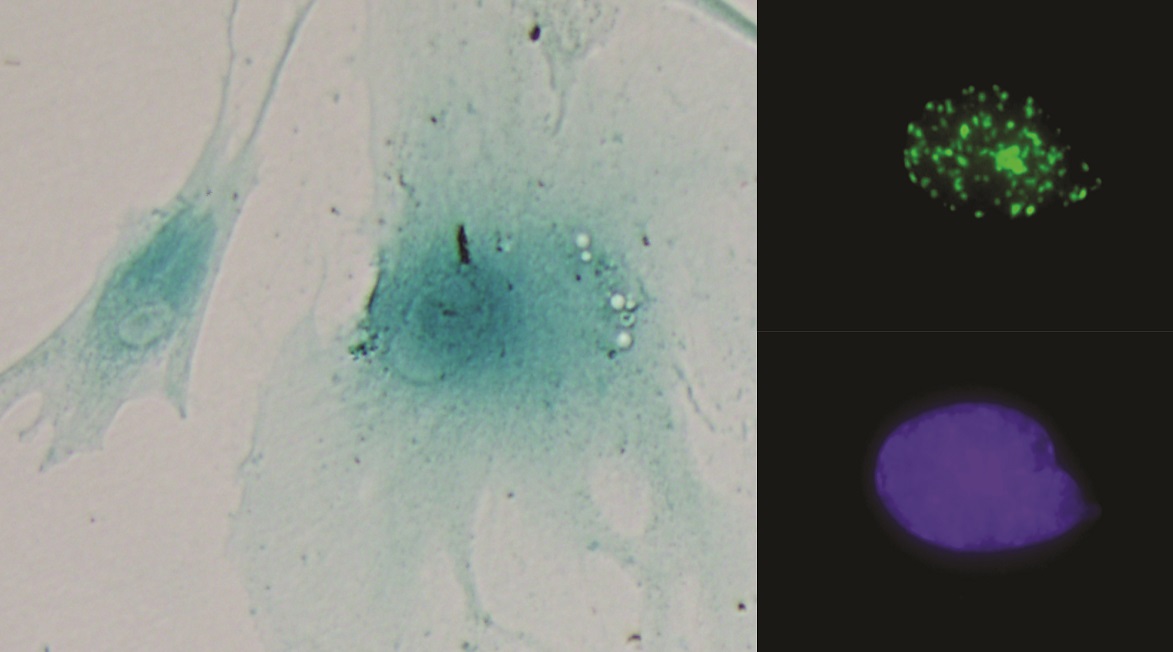

Imágenes de dos células senescentes (izquierda). A la derecha un núcleo celular mostrando foco de daño al ADN (arriba) y su control (abajo).

Según explica Amancio Carnero, “la senescencia consiste en una parada de la división celular de las células que lo sufren, pese a lo cual estas son capaces de secretar una serie de factores que aumentan la capacidad tumorigénica de las células tumorales. Esto provoca que se establezca un circuito entre células tumorales y las que no lo son, que conduce a un aumento del número de células madre tumorales, las cuales poseen una capacidad proliferativa mayor que las células tumorales normales y son capaces de aumentar la resistencia a terapias antitumorales”.